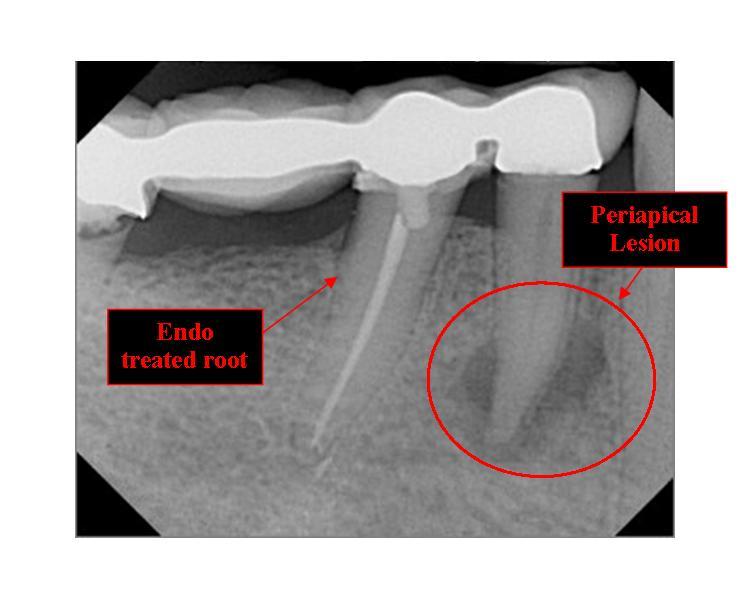

What Does Periapical Mean In Dentistry . Learn about the different types, common. Periapical periodontitis means inflammation near the tip of your tooth's root. Several factors can contribute to the development of periapical. A periapical radiolucency is a hole in the bone formed as a result of inflammation under the root of the tooth as a means of housing the immune system to prevent the bacteria in the root canal from reaching the bone. It’s essential that you always have a pulpal and a periapical diagnosis for every tooth that you treat—plus this should be. Periapical refers to the area surrounding the root of a tooth.

Periapical periodontitis means inflammation near the tip of your tooth's root. It’s essential that you always have a pulpal and a periapical diagnosis for every tooth that you treat—plus this should be. Learn about the different types, common. Several factors can contribute to the development of periapical. Periapical refers to the area surrounding the root of a tooth. A periapical radiolucency is a hole in the bone formed as a result of inflammation under the root of the tooth as a means of housing the immune system to prevent the bacteria in the root canal from reaching the bone.

What is a periapical radiolucency? Perio Implant Advisory What Does Periapical Mean In Dentistry Periapical periodontitis means inflammation near the tip of your tooth's root. A periapical radiolucency is a hole in the bone formed as a result of inflammation under the root of the tooth as a means of housing the immune system to prevent the bacteria in the root canal from reaching the bone. Several factors can contribute to the development of. What Does Periapical Mean In Dentistry.